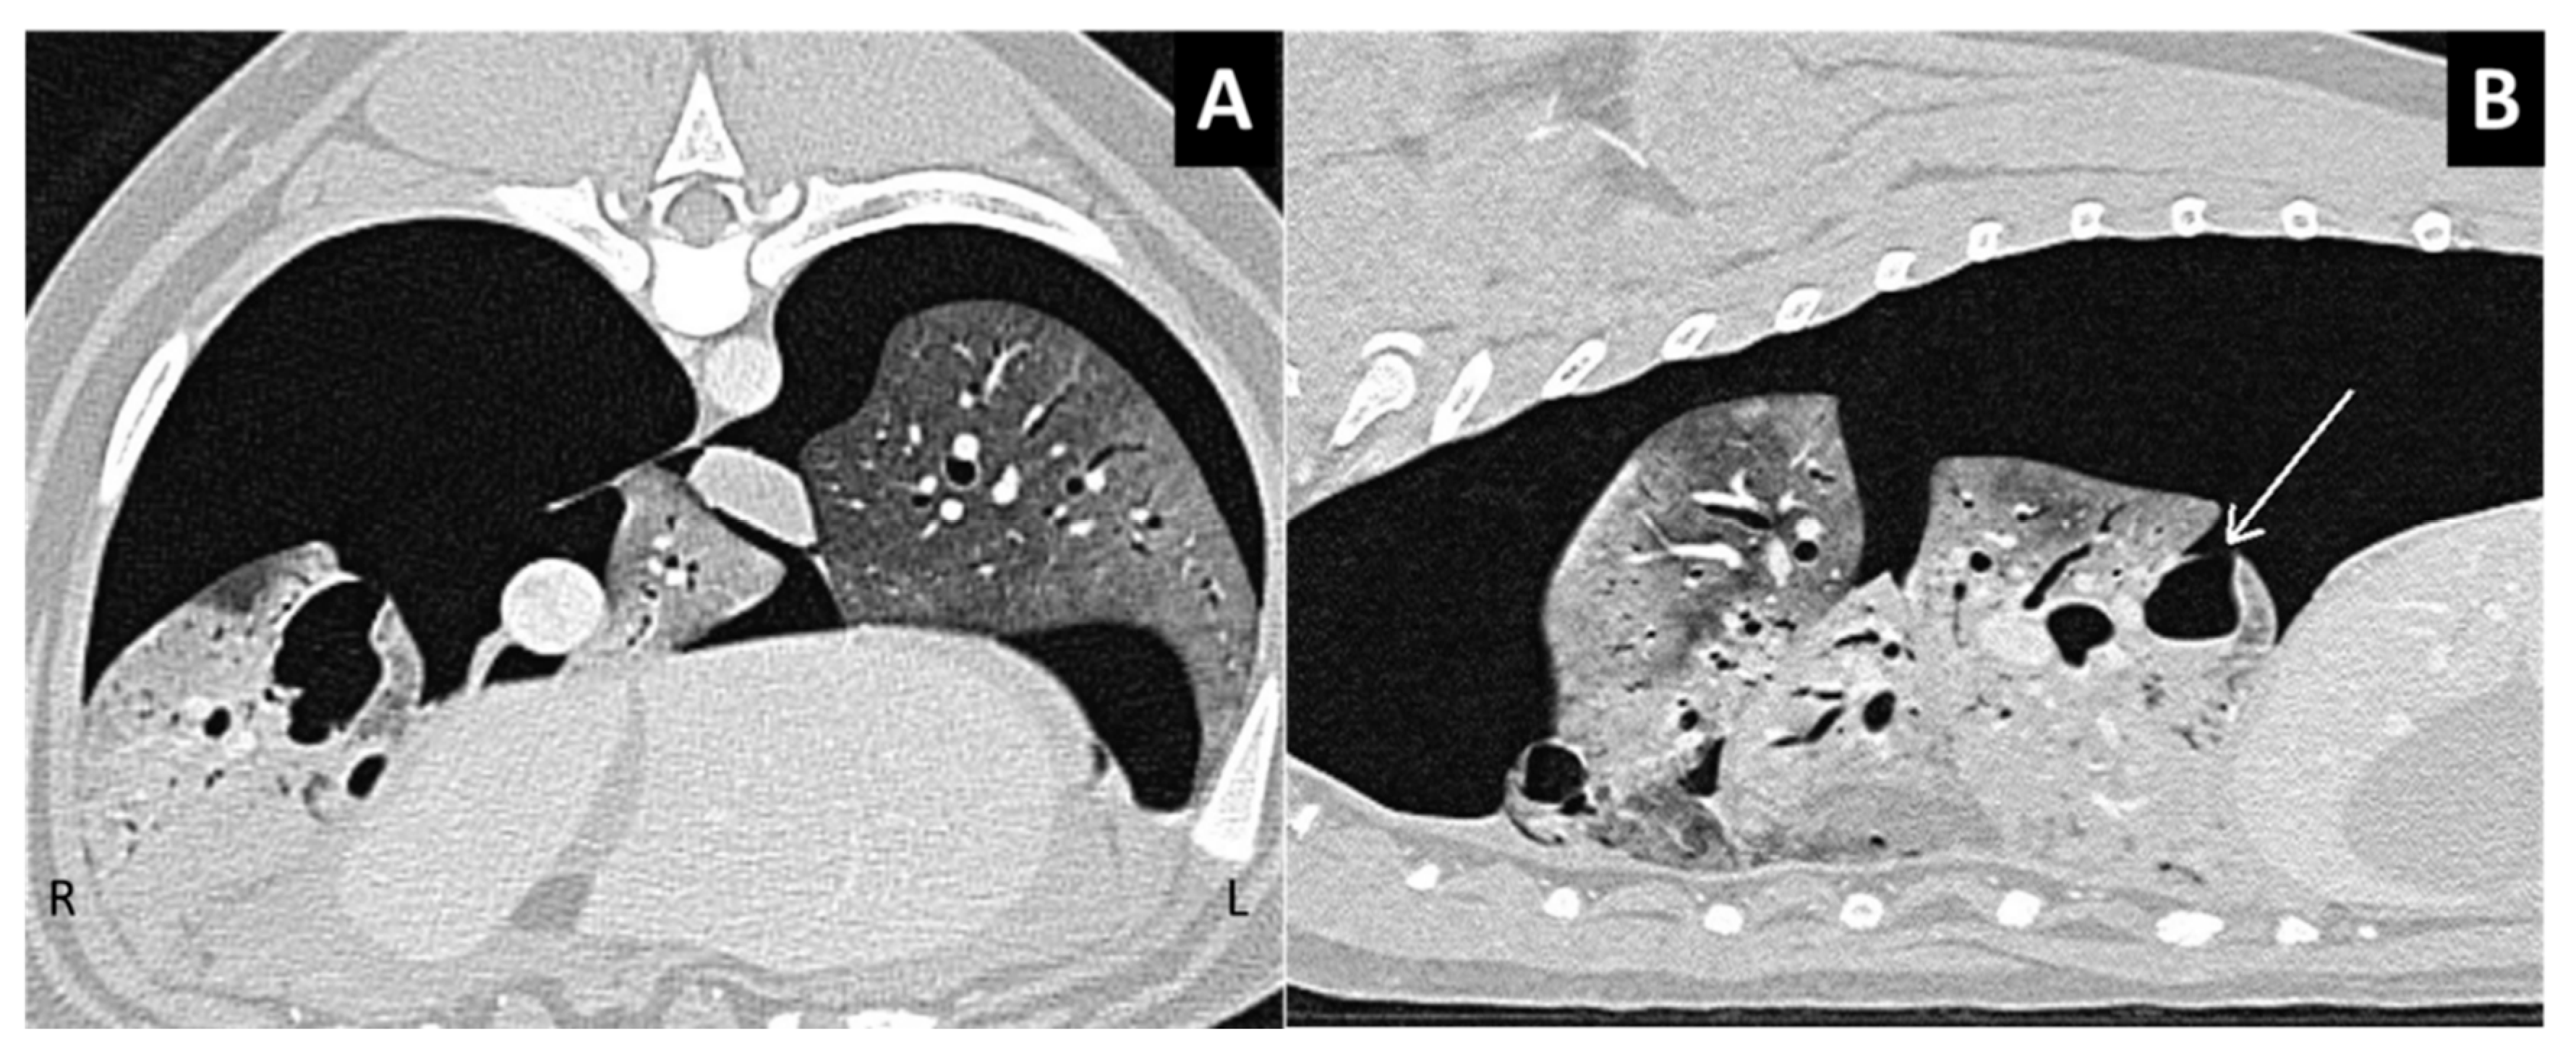

Figure 3.

Type 1 and Type 2 lung lacerations. (A) The transverse section of the thorax in a traumatized dog. In the left lung, there are two ovoid pseudocystic lesions, one located deep in the lung parenchyma and another in the subpleural area of paraspinal region, not associated with spinal fracture. Note the air–fluid level in the deep lesion in (A) and in the superficial lesion in (B) (pneumohematocele). Pneumothorax is present on the right side. (B) The transverse section of another traumatized dog with small Type 1 and Type 2 lung lacerations, both with mixed air–blood content. The dog had no vertebral fractures.